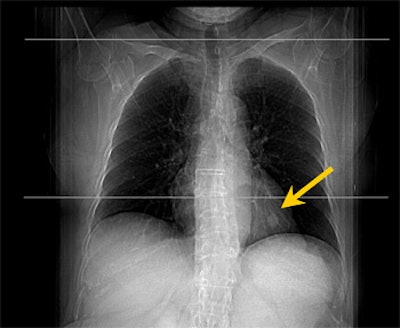

![]() |

| CT image of suspicious 1.4-cm pulmonary nodule in left lower lobe. |